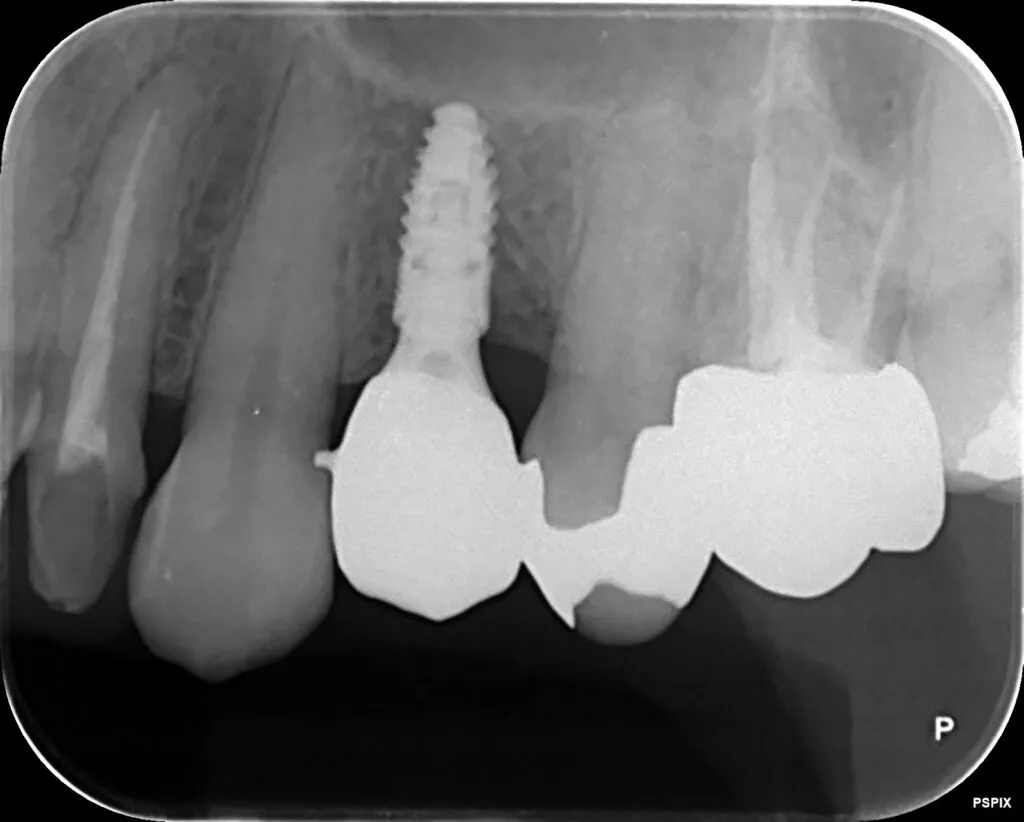

インプラント治療症例①

インプラント治療症例②

インプラント治療症例③

インプラント治療症例④

インプラント治療症例⑤

インプラント治療症例⑥

歯周病などで骨が少なくなった患者さんに対して行う、骨を再生させる処置(ソケットプリザベーション)